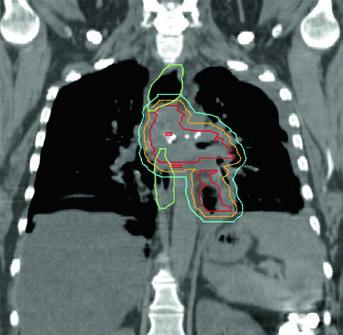

Linfoma de Hodgkin e Não Hodgkin

O capítulo de linfoma se destaca por organizar campo e volume lado a lado. Os autores partem de princípios gerais de delineamento e field setup, passam para radioterapia em sítio envolvido e em linfonodo envolvido, entram em exemplos baseados em casos e terminam com contornos para regiões inguino-pélvicas, estômago e linfoma orbitário ou sinonasal. Para revisar esse percurso, veja o artigo dedicado ao linfoma.